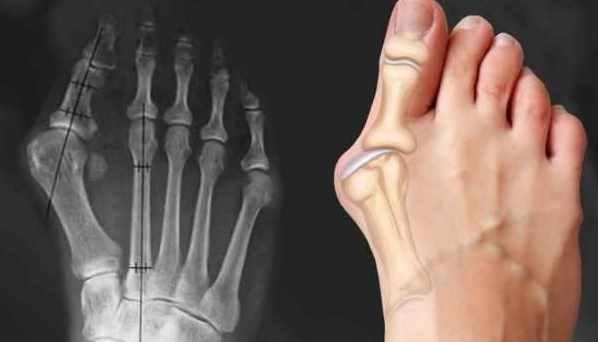

▫️Халюкс вальгус